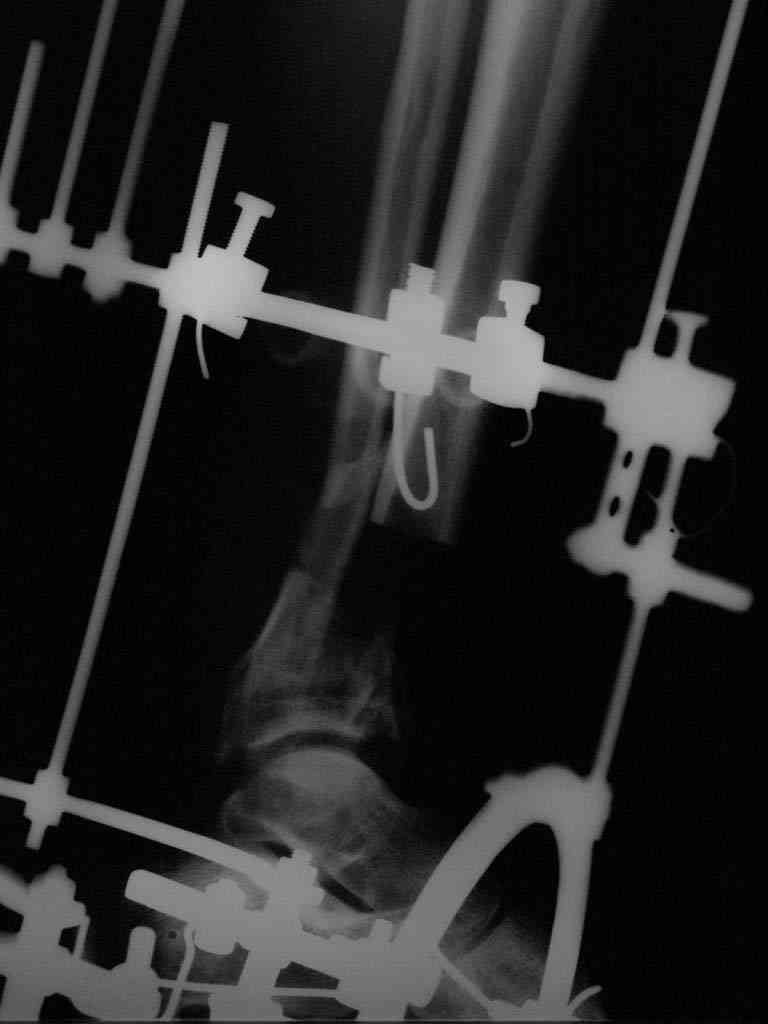

аппарата наружной фиксации (см. Р-граммы). Отломки сближены на 2 см (остеотомию малоберцовой не делали). В настоящее время (5 сутки после операции) незначительное количество серозного отделяемого из раны, имеется дефект кости 4 см

(см. Р-граммы).

В последующем склоняемся к перемонтажу аппарата наружной фиксации, остеотомии малоберцовой кости в области повреждения, сближении отломков. По заживлению раны удлинение левой голени на 4 см. Однако, некоторыми высказывалось мнение о необходимости артродеза.

Представляем рентгенограммы левой голени при поступлении, после повторного оперативного лечения и фото st.localis на 14.11.08.